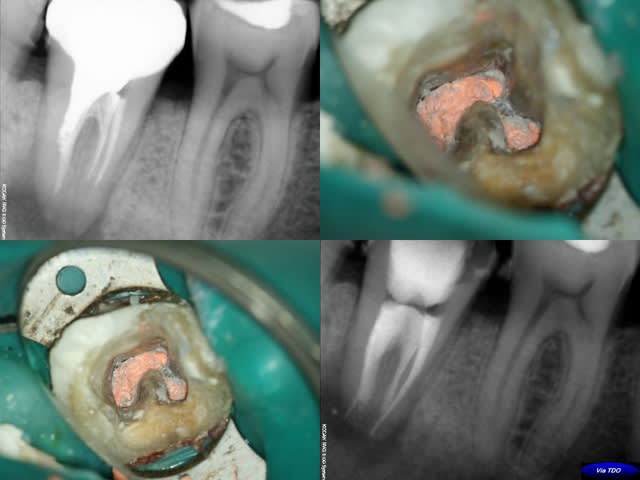

Je veux dire des vrqis, enfin des trucs comme celui-ci.

Canal en c b39gal - Eugenol

jerome elias

30/01/2009 à 20h21

Très Joli , tu l'as obturé comment?GFlow et thermF?

Compaction verticale a chaud en technique de Schilder